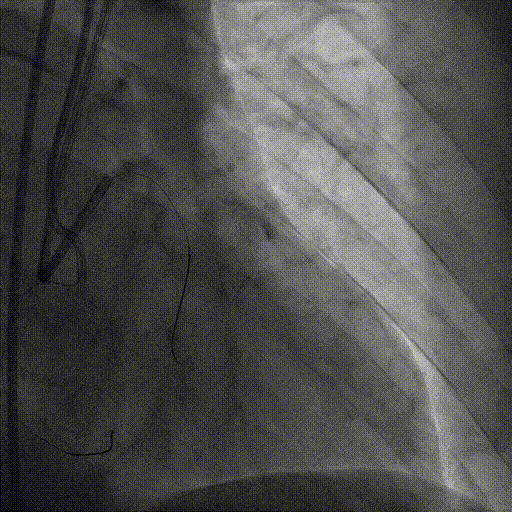

术前造影

术后造影